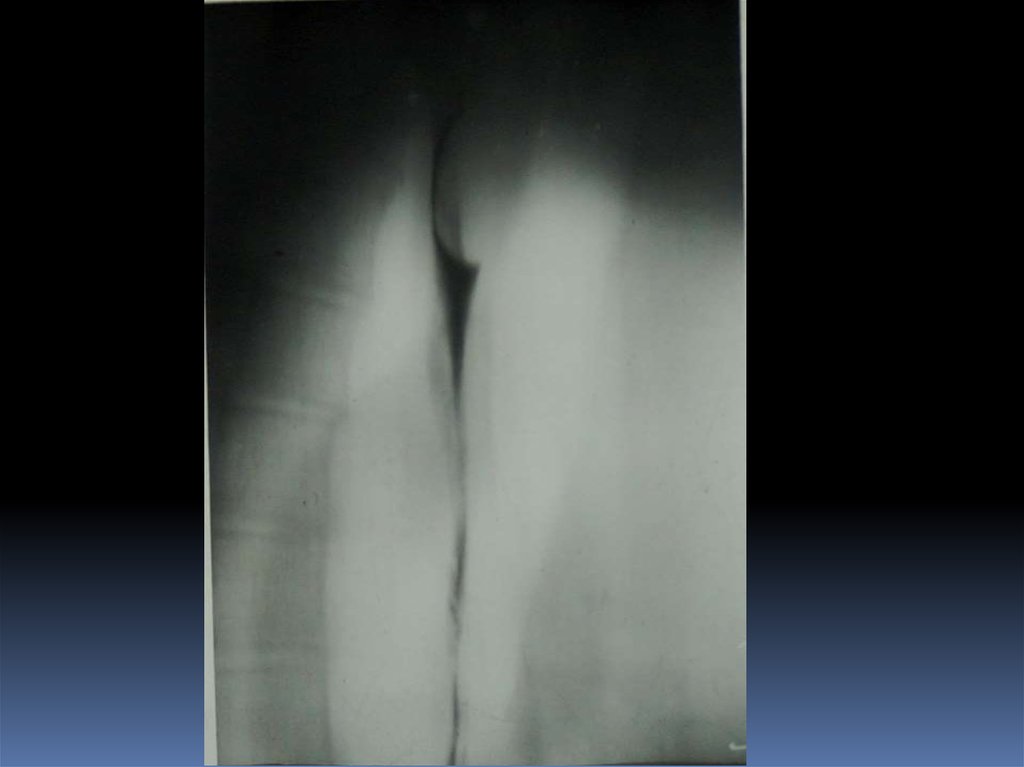

16. Рентгенодиагностика рака желудочно-кишечного тракта

Рентгенодиагностика

рака желудочнокишечного тракта

17. Классификация рака органов ЖКТ

1. Экзофитная форма:

2. Эндофитная форма:

узловая форма;

диффузноинфильтративная

форма;

полипоподобная

чашеподобная форма. инфильтративноязвенная.

3. СМЕШАННАЯ ФОРМА – 10-15%